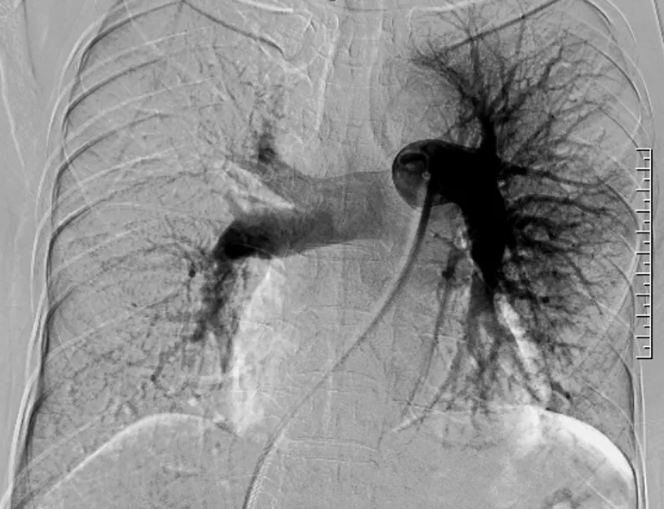

图6. 心脏超声 2025-3-19

患者拟诊CTEPH,按照CTEPH诊断流程(图3),完善CTPA(图4):右肺动脉分支远端显示不清,肺灌注显像(图5):左肺上叶及右肺大片状血流灌注减低/缺损,心脏超声(图6):右心扩大(右室前后径22mm,右房58×55mm)、TAPSE 24mm、三尖瓣轻度关闭不全(峰值流速4.5m/s)、肺动脉高压(重度,估测肺动脉收缩压99 mmHg)。右心导管检查结果示:mPAP 76/33(47)mmHg,CI 1.6L/min/m2,PVR12.3WU,SvO2:61.4%,RAP:8mmHg。肺动脉造影可见:双侧肺动脉及其分支广泛狭窄、闭塞病变,远端血流差,以右侧为重,血流多为0-1级(图7)。

图7 肺动脉造影